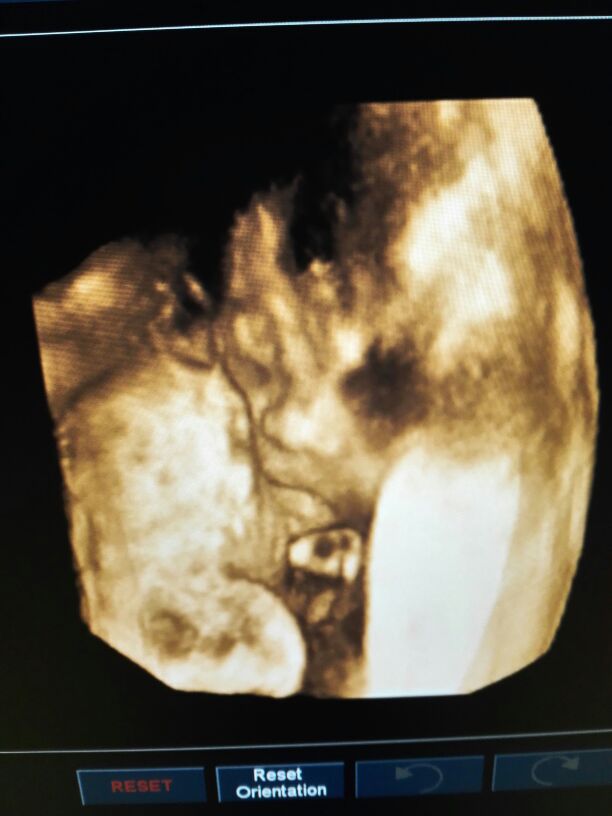

查体:神志模糊,刺痛睁眼,回答错误,刺痛定位,GCS计11分(E2V5M5);双侧瞳孔等大等圆,直径约3mm,对光反射灵敏,左侧外耳道见血性液体流出,双肺稍闻及湿罗音,四肢肌力良好5级,四肢肌张力正常。颈项抵抗、Kerning's征、Brudzinski征阴性。辅助检查:2016年01月05日我院颅脑及胸部CT示:左侧颞骨骨皮质不连续。左侧颞部颅骨内板下见弧形高密影,最厚约2cm;双侧颅骨内板下见广泛新月形高密影。双侧颞叶见散在结节及斑片状高密影,较大者约0.8cm×0.7cm。脑室系统及中线结构无变形、移位。两肺纹理增粗,透亮度欠均匀,右肺上中叶见局限性透亮影;两肺胸膜下见斑片状、点状阴影,所见各支气管腔通畅,肺门及纵隔未见肿大淋巴结,胸膜无增厚,胸腔内无积液。